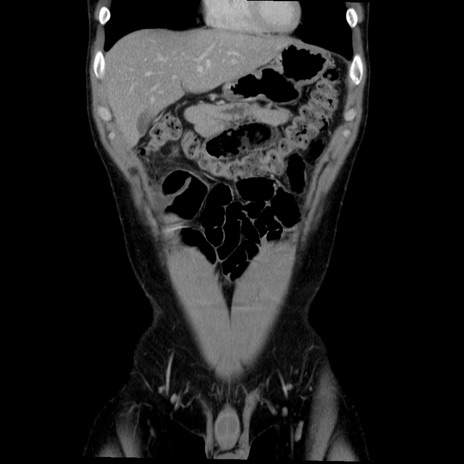

症例36(冠状断像)

【症例】20歳代 男性

【主訴】心窩部痛

【現病歴】今朝より上腹部痛あり。一旦軽快していたが再度出現したため救急要請。昨日夕に白身の魚を含む刺身を食べた。

【身体所見】BP 136/89mmHg、HR 74/min、BT 37.0℃、腹部:膨満、軟、心窩部に圧痛あり。反跳痛なし、筋性防御なし、腸雑音やや亢進あり。

【データ】WBC 17700、CRP 0.48